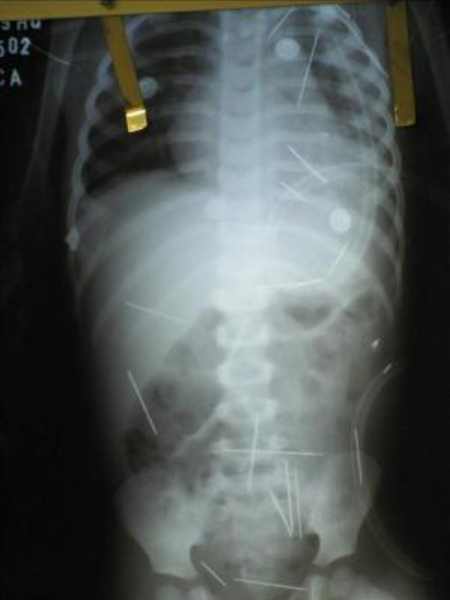

Radiografía del estómago del niño con las agujas clavadas

El pasado viernes el menor fue sometido a una intervención quirúrgica en la que le fueron retiradas cuatro agujas, que estaban alojadas cerca del corazón y de los pulmones.

Los médicos han dicho que durante los próximos días deberán realizar otra operación para extraer otras agujas que se encuentran en las proximidades del abdomen, la vejiga y el aparato digestivo.

Hasta ahora, los responsables por la atención del pequeño no han podido determinar con exactitud cuántas agujas le fueron clavadas.

Inicialmente se habló de unas 50, luego de 42 y ahora se cree que fueron 31, por lo que aún tendría, por lo menos, 27 agujas dentro de su cuerpo.